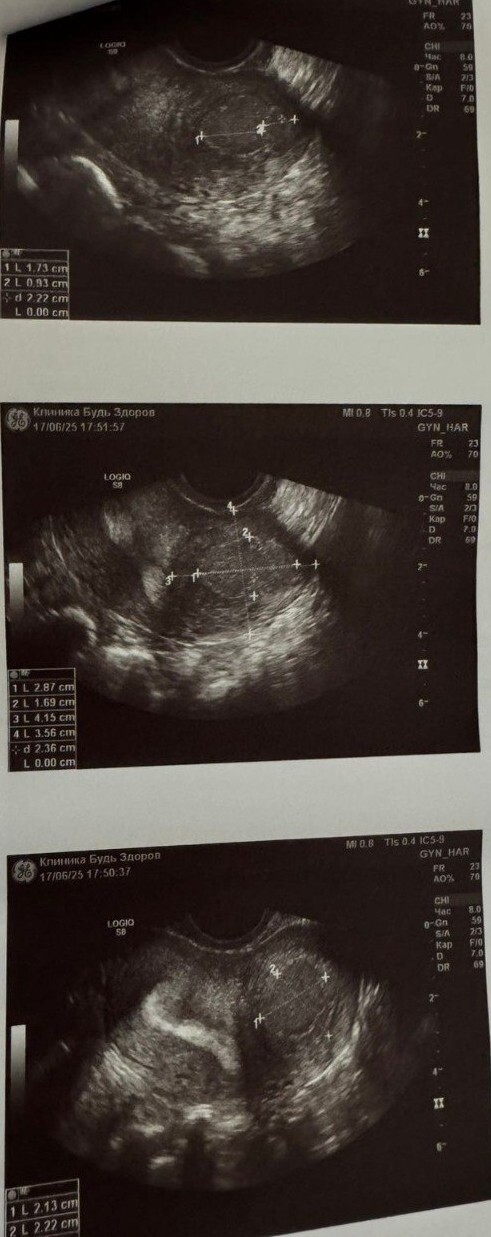

По данным УЗИ малого таза выявил кисту матки (жидкостное образование 40х50 мм. с толстыми стенками с характерным мелкодисперсным содержимым). Признаков кровотока в стенке образования не обнаружено. Так же отмечена диффузная неоднородность миометрия (признаки аденомиоза).

Через десять дней после операции УЗИ органов малого таза показало, что тело матки не увеличено, при этом швы лежали хорошо, гематом и воспалений не было, полость матки, яичники и маточные трубы были в норме. В этот же день пациентку в хорошем состоянии выписали домой. Для предотвращения рецидива заболевания пациентке рекомендован приём Диеногеста (Визанна, Зафрилла).